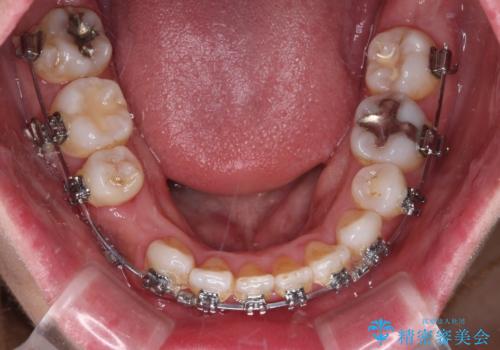

- 矯正装置

- メタルブラケット

- 上下前歯のデコボコを気にして来院された患者様です。

右上と左下の小臼歯が1本ずつ欠損しており、奥歯の咬み合わせが乱れている状態でした。

バランスを取るために右下と左上の小臼歯を1本ずつ抜歯し、移動のための固定源としてアンカースクリューを利用してワイヤー装置による矯正治療を行うこととしました。